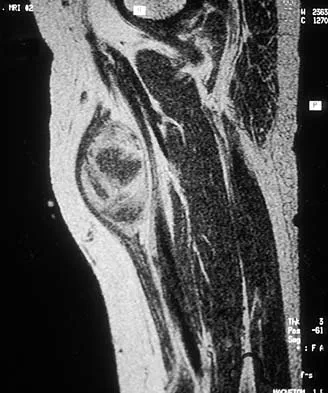

Figures 30a and 30b show the MRI scans of a 51-year-old woman who has had an enlarging soft-tissue mass in her right thigh for the past 18 months. Examination reveals no inguinal adenopathy. Results of a biopsy show a high-grade sarcoma. A bone scan is unremarkable, and a CT scan of the chest shows no evidence of pulmonary metastasis. According to the Musculoskeletal Tumor Society (MSTS) staging system, the tumor should be classified as what stage?

Explanation